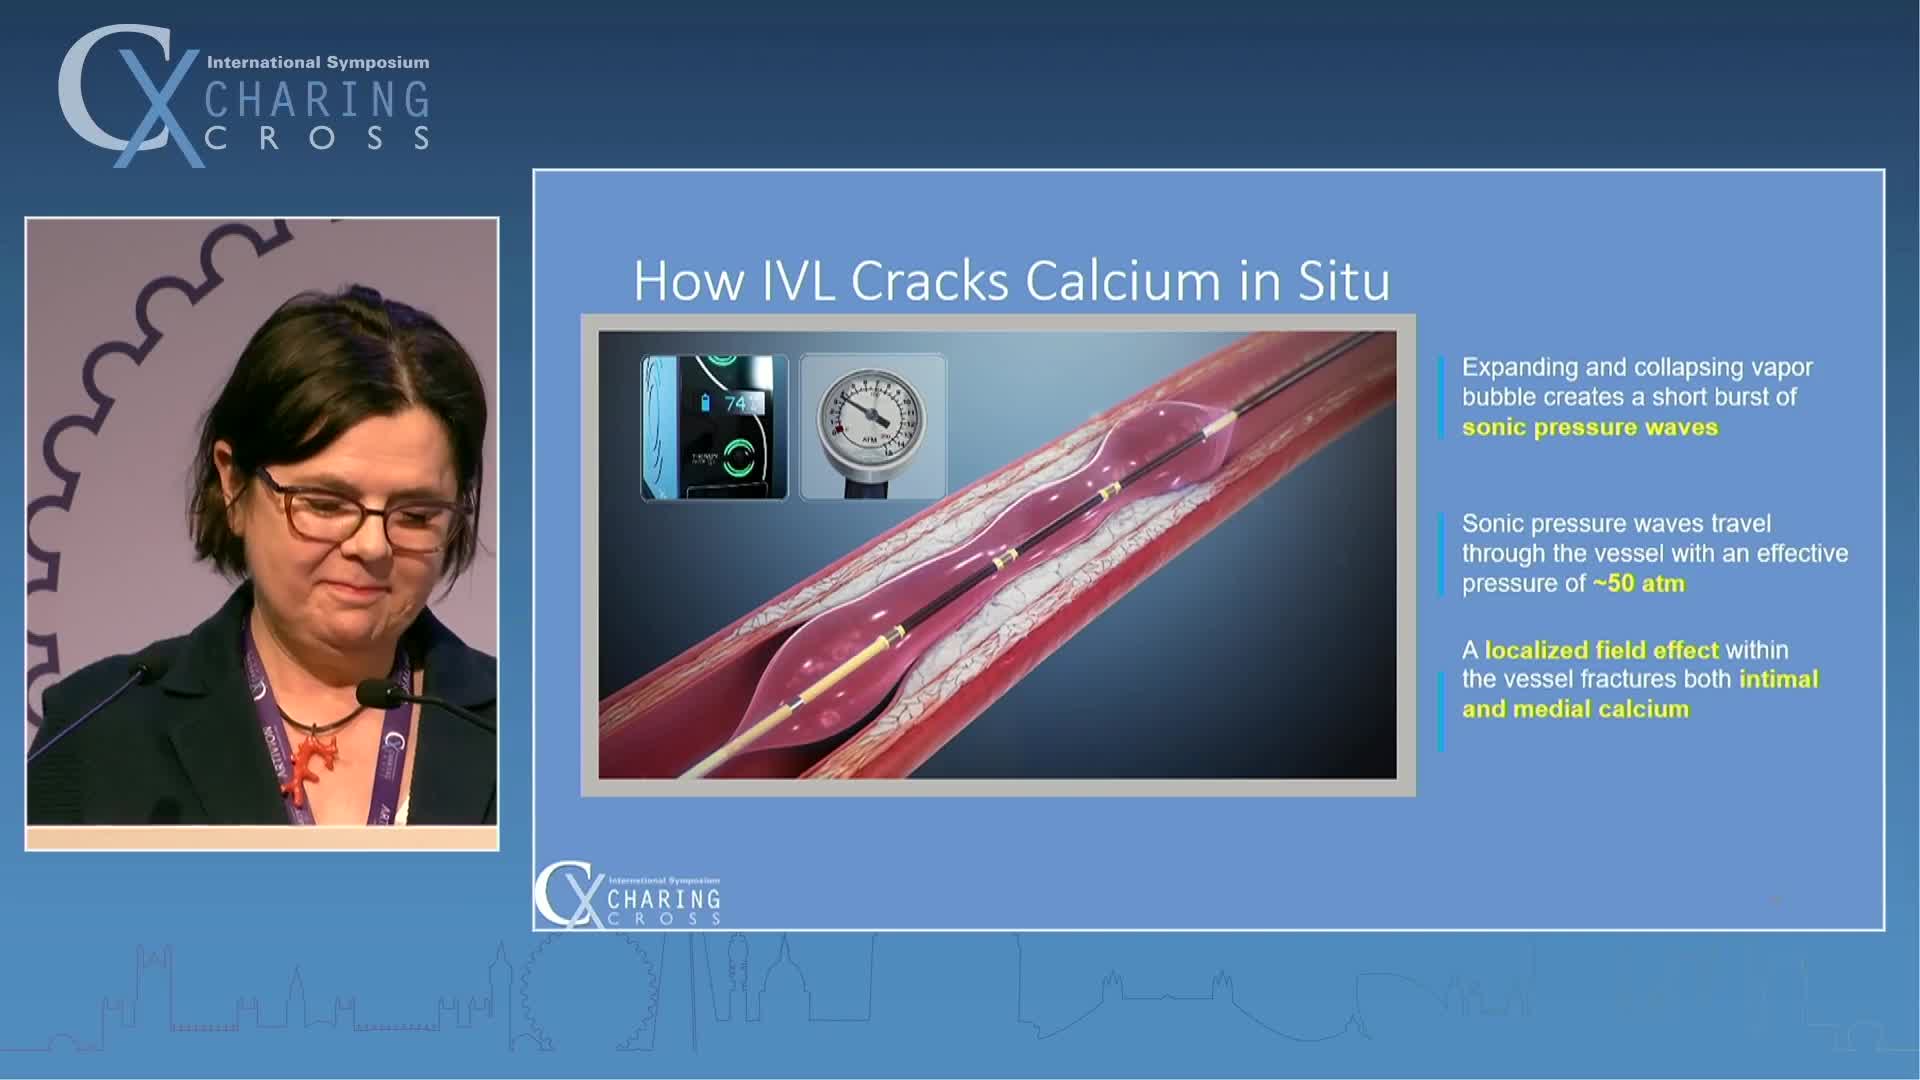

Simplify your procedures with Intravascular Lithotripsy (IVL) by safely modifying intimal and medial calcium to achieve optimal outcomes while minimising trauma, complications and costs due to its unique MOA.

IVL cracking the calcium conundrum in PAD

Peripheral IVL from the Renals to the Toes